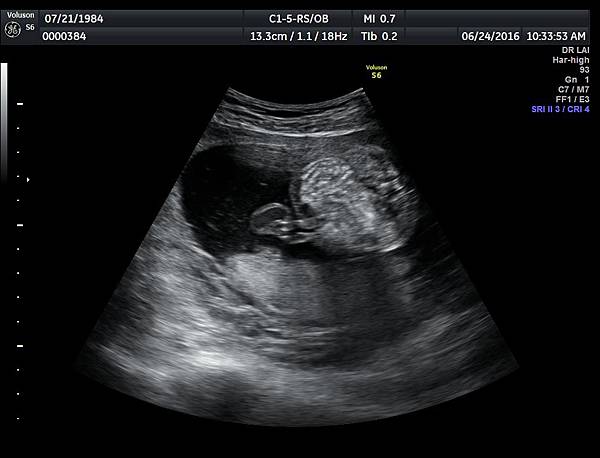

6月24日在我的診所,我幫一位懷孕22週31歲的孕婦看高層次超音波,發現胎兒的腸子很白,形狀也特別的怪( 附圖 1~12 ),我建議她做進一步相關的檢查,包括抽羊水檢查等等。